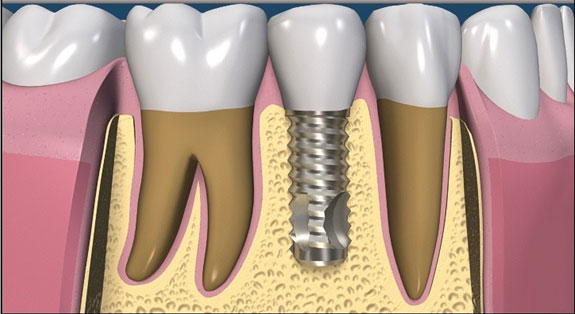

Dental Implants in Karachi: What You Actually Need to Know

Losing a tooth changes more than you expect. It's not just about the gap in your smile, though that's uncomfortable enough on its own. It affects how you chew, how you speak, how confident you feel in a conversation, and over time, it can affect the health of the surrounding teeth and jawbone in ways [...]

Dental Implants at Altamash Dental Clinic: Smiles Re-made, Confidence Restored

We’ll all sooner or later, at one time or another, lose a few teeth here and there, to decay, to an accident, or just to wear and tear

Smile Strong: Why Dental Implants Are the Gold Standard in Tooth Replacement

Missing teeth not only affect your appearance—they also impact your speech, eating, and confidence. At Altamash Dental Clinic, we believe everyone deserves a full, confident smile. Dental implants offer a natural-looking, permanent solution that feels just like real teeth. In this article, we will discuss what implants are, the benefits they offer, and why Altamash [...]

Why Dental Implants by Altamash Dental Clinic are the Best Option for Your Smile

Lost teeth can ruin your smile, besides ruining your self-confidence, oral well-being, and quality of life. Dental implants offer a permanent way to revive your smile and function. Altamash Dental Clinic employs experts to provide high-quality implants tailored to your specific requirements. Whether you are missing a single tooth or many, our trained staff aims [...]

Say Goodbye to Gaps: Transform Your Smile with Dental Implants at Altamash Dental Clinic

With dental implants, a missing tooth in the oral cavity can now be restored using some of the most advanced prosthetic solutions.